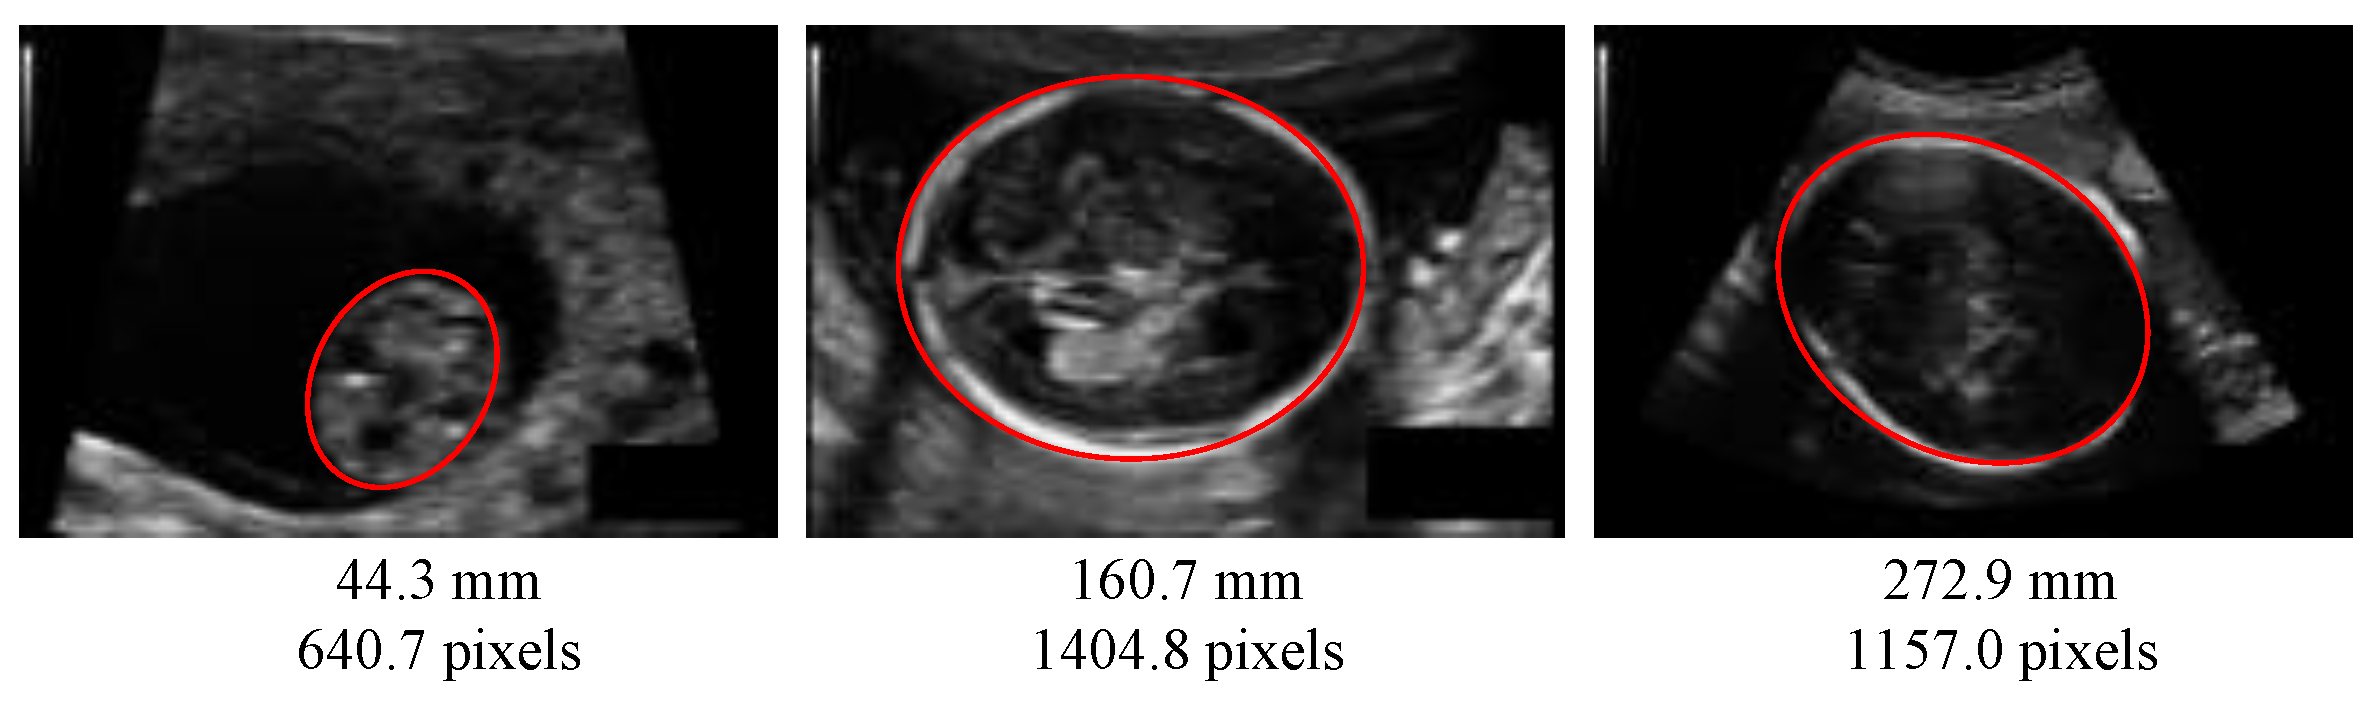

The automated measurement of fetus head circumference (HC) is performed throughout pregnancy as a key biometric to monitor fetus growth and estimate gestational age. In a clinical routine, this measurement is performed on ultrasound (US) images, via manually tracing the skull contour, along to fitting it to an ellipse, which is done by sonographers. Figure 1 is one sample of an ultrasound (US) image of fetus head from the HC18 public dataset [1] used in this paper. Identifying the head contour is challenging due to low signal-to-noise ratio in US images, and also because the contours have fuzzy (and sometimes missing) borders (Figure 1). Manual contouring is an operator-dependant operation, subject to intra- and inter-variability, which yields inaccurate measurements, as measured in [2]: The 95% limits of agreement have been measured to ±7 mm for the intra-operator variability and ±12 mm for the inter-operator variability.

Figure 1.

Ultrasound images of fetus head from the HC18 dataset [1] at different pregnancy stages. Red ellipses are head contours. Below the image, the corresponding head circumference (HC) is given. Images may have a different pixel size.